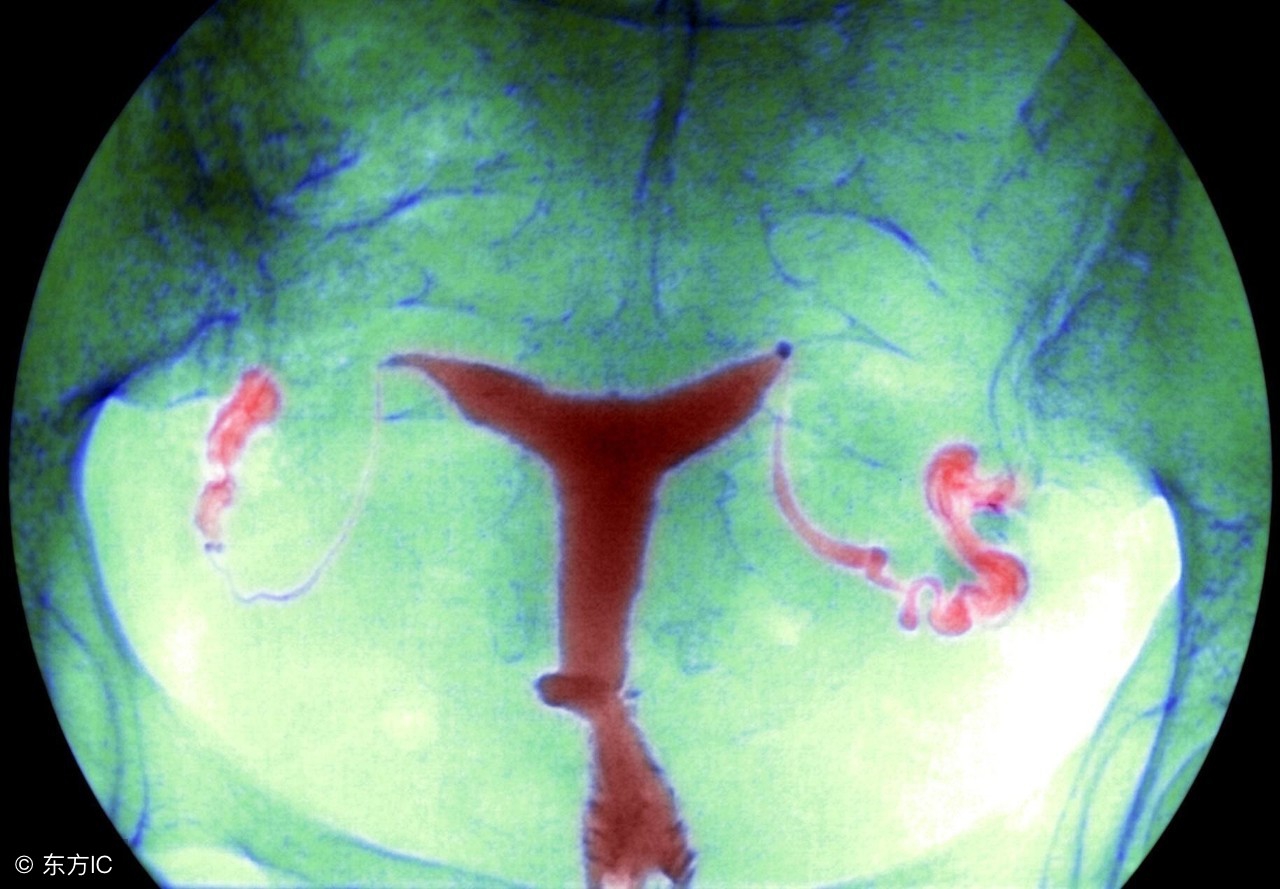

3、还有盆腔一侧积液形成囊肿,多伴有输卵管积水堵塞可能,需要进一步输卵管通液或者造影检查;

需要明确的是,盆腔积液疾病并非是一个病名,而仅仅是描述了一种生理现象,其是指女性盆腔里面有一定的液体存在。在临床上,一般将盆腔积液被分为一下两种类型。

生理性的盆腔积液会在女性的月经期和排卵期出现,这种情况下的盆腔积液一般积液深度会小于30mm,但是此时的积液会在月经期或排卵期过后自动消除。

相比较之下,病理性盆腔积液出现的最常见原因为患者有盆腔炎,也可能因为流产后或手术后感染,或盆腔肿瘤引起的腹水。对于这样的盆腔积液情况,其一般在临床上是需要进行治疗的。